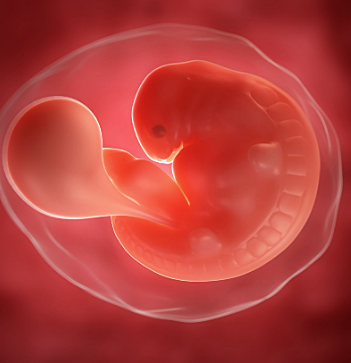

• Semana 6

Semana 6

En la 6 semana del embarazo ocurren cambios.El embrión ya mide entre 2 y 4 milímetros en la 6 semana de embarazo. Este es el comienzo del periodo embrionario, se produce la formación de la mayoría de los órganos y en este momento es que se forman las malformaciones